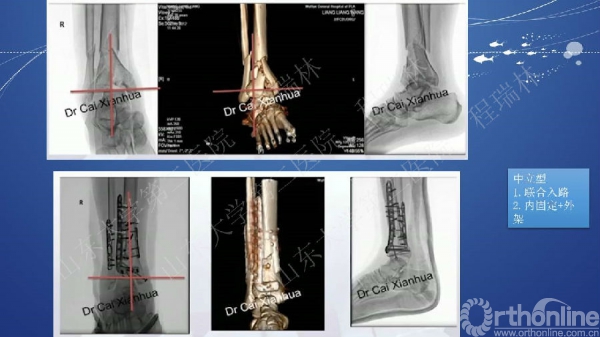

Pilon骨折的手术基本原则

Pilon骨折是踝部的复杂骨折,以高能量损伤、不稳定、软组织损伤严重为特点。手术复杂,并发症常见且严重。一旦治疗失败,常常带来灾难性的后果,如截肢、严重创伤性关节炎后期再关节融合等。

Pilon骨折的治疗目的:软组织保护,恢复下肢力线,解剖复位关节面。